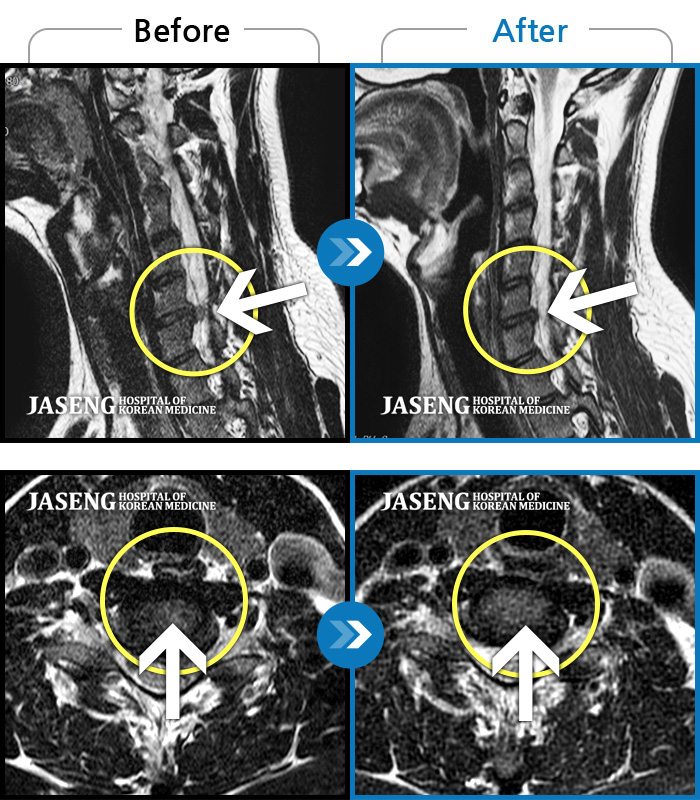

• 목디스크